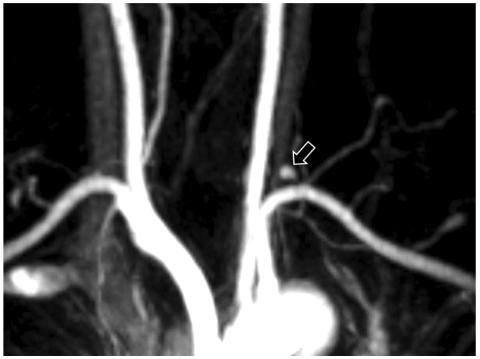

Coronary artery aneurysms are uncommon, are usually associated with atherosclerosis, and rarely involve all three major coronary arteries. The present report describes a rare case of a young female patient presenting with acute myocardial infarction (AMI). Coronary angiography revealed multiple severe aneurysmal and stenotic changes. Based on clinical feature and angiographic findings, it was strongly suspected that the patient had polyarteritis nodosa (PAN) complicated by AMI. The patient was treated with standard cardiac medications and immunosuppressive agents and has remained stable without further complications during a follow-up period of 6 months.

冠状动脉瘤并不常见,通常与动脉粥样硬化有关,很少累及所有三支主要冠状动脉。本报告描述了一例年轻女性患者急性心肌梗死(AMI)的罕见病例。冠状动脉造影显示多处严重的动脉瘤样和狭窄性改变。根据临床特征和血管造影结果,强烈怀疑患者患有结节性多动脉炎(PAN)合并 AMI。患者接受了标准的心脏药物和免疫抑制剂治疗,在 6 个月的随访期间病情稳定,没有进一步的并发症。